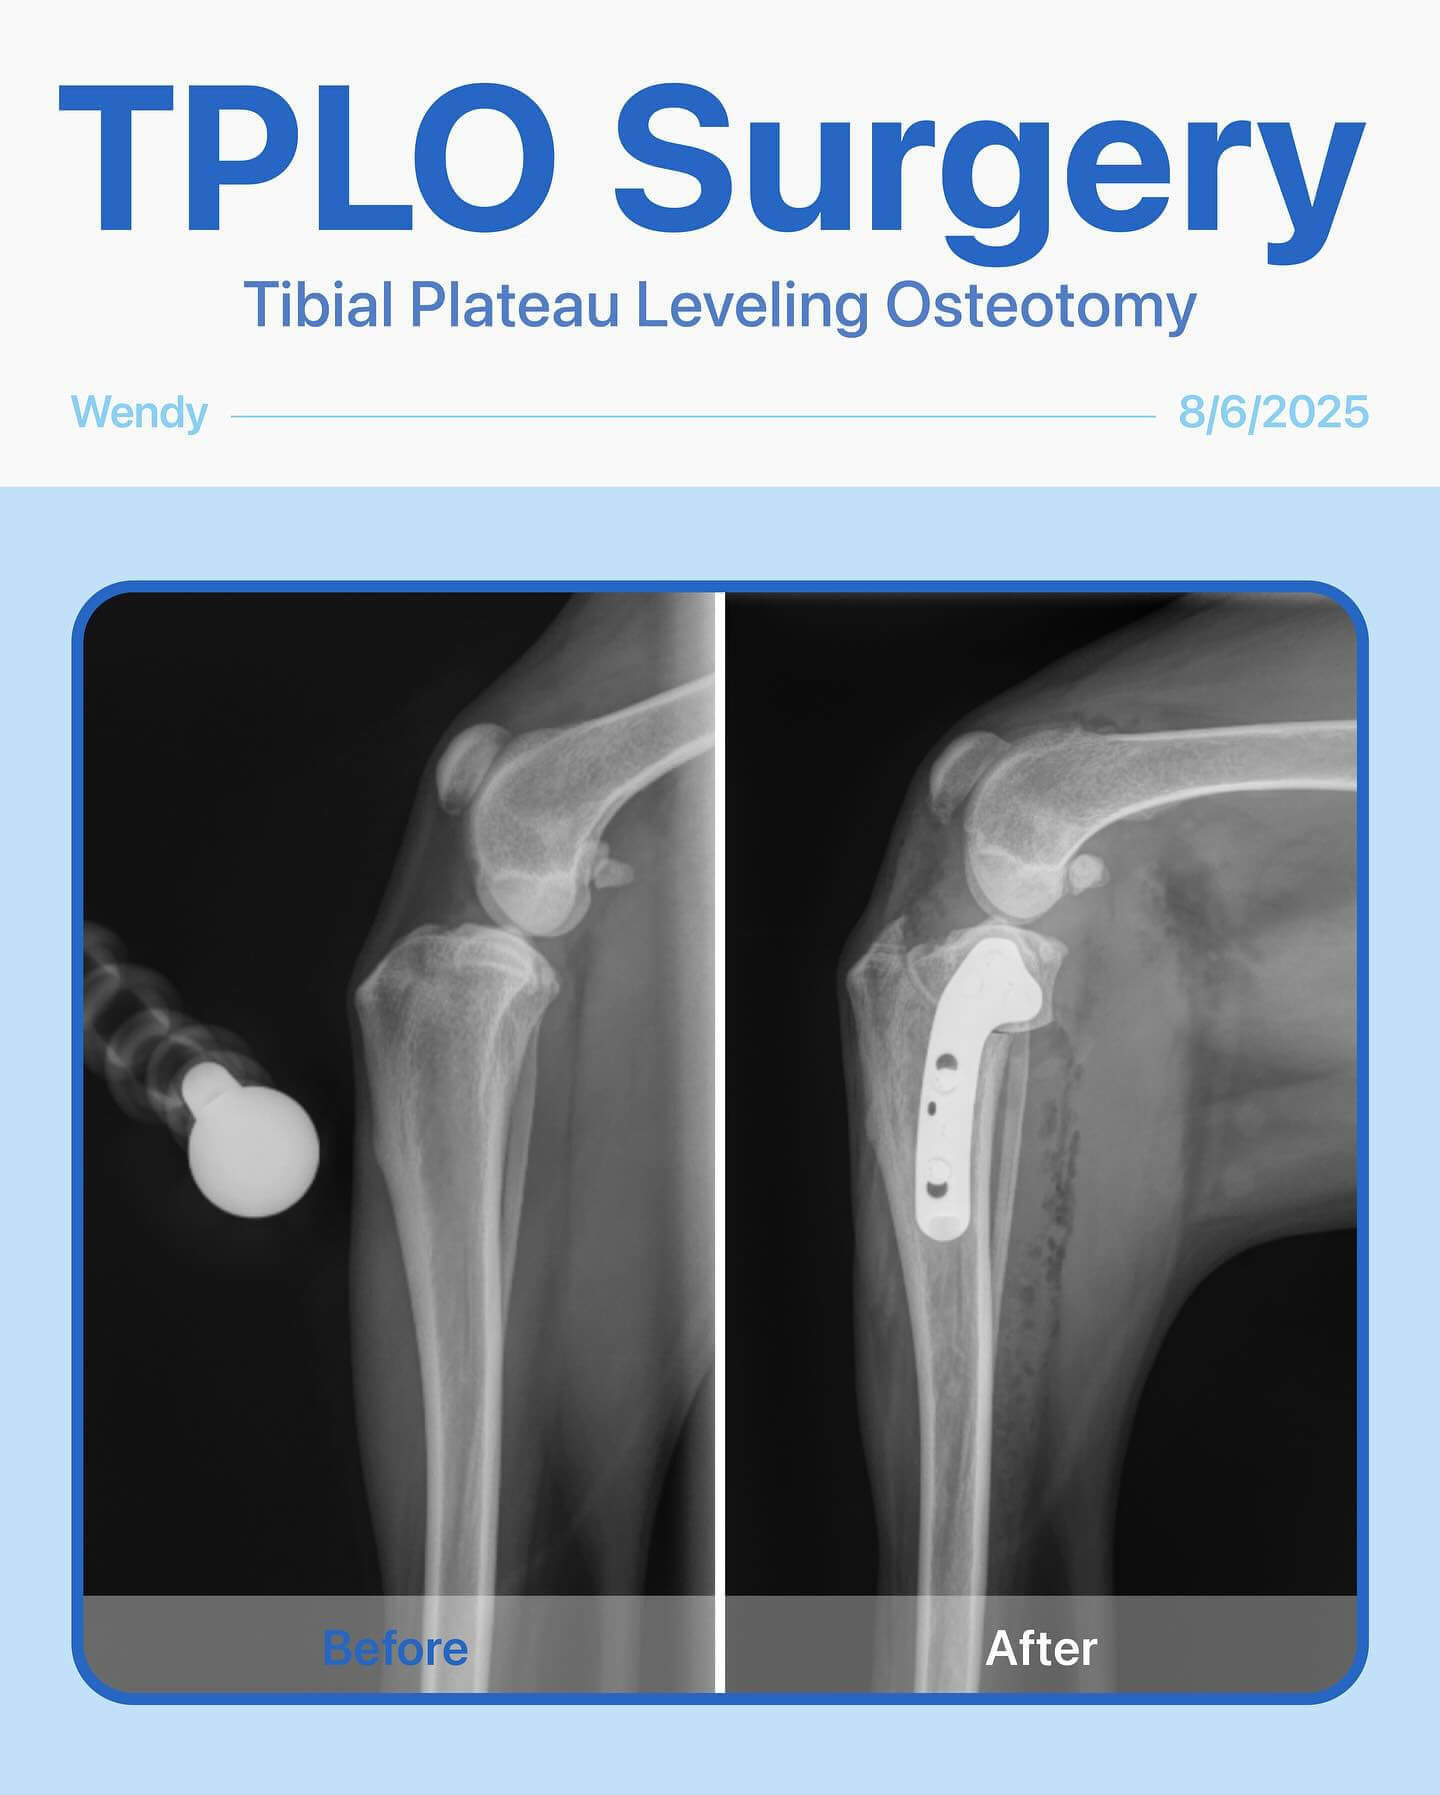

Stronger Than Ever: Wendy’s Story. Last year, Wendy, our brave 7-year-old English Shepherd, had a TPLO surgery on her back left leg. Recently, her back right leg started limping, and after a careful exam, we found that she needed another TPLO surgery.

The surgery went smoothly, and Wendy is now on the road to recovery, already showing her resilience and happy spirit. We’re so proud of her!